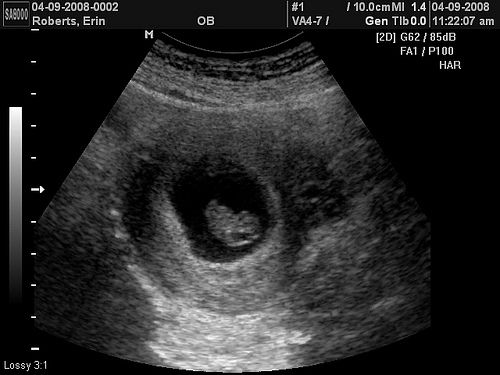

USG in Pregnancy